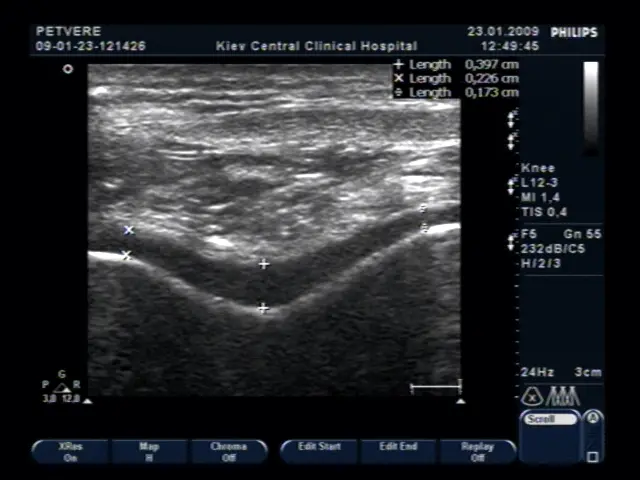

УЗД коліна — достатньо точний метод діагностики патології м’ягких тканин суглоба. УЗД дозволяє бачити запалення, уточнювати стан синовіальнї оболонки, об’єм рідини в коліні, її локалізацію і ті.

Оцінка стану суглобового хряща коліна, що вкрай важливо при артрозі (фото нижче).

Оцінка кровотоку в синовіальній оболонці колінного суглоба